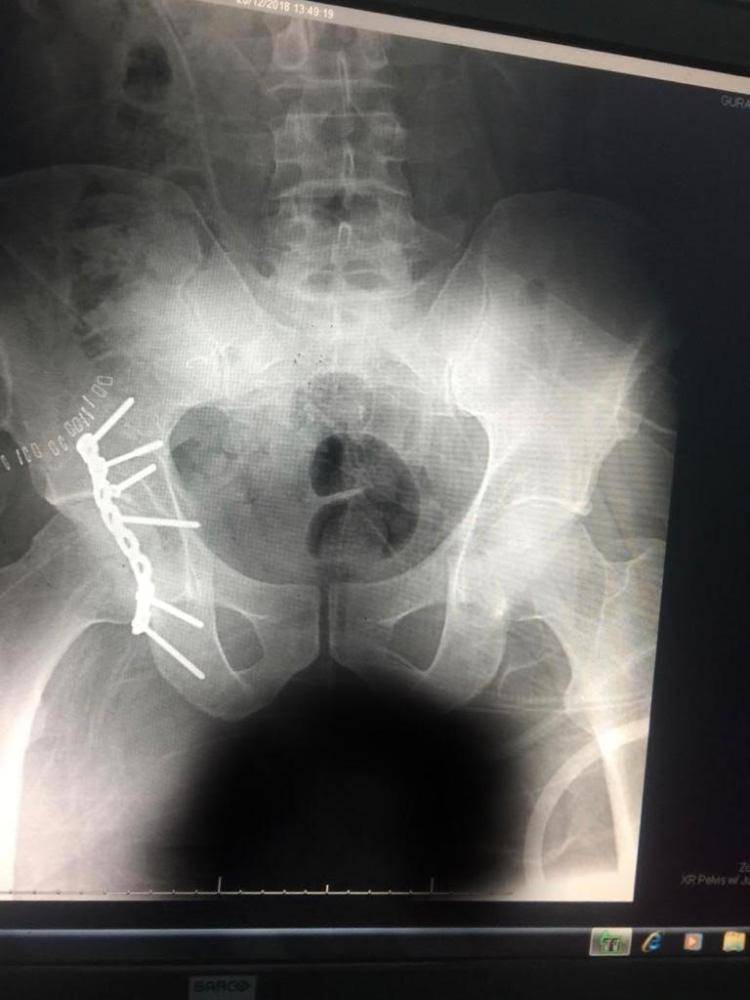

وعلى الفور، قام فريق طبي بقيادة استشاري جراحة العظام بإجراء عملية عاجلة لعلاج الكسور، حيث كانت الإصابة خلع ورك زيمن مع كسر خلفي مفتت في الجوف المفصلي للورك الأيمن.

وأضافت أنه تم التثبيت الجراحي بشريحة إعادة بناء مع براغٍ مقفلة، علماً أنها من العمليات الكبرى التي يتم إجراؤها بالمستشفيات التخصصية وتم إجراؤها بمستشفى القريات العام.